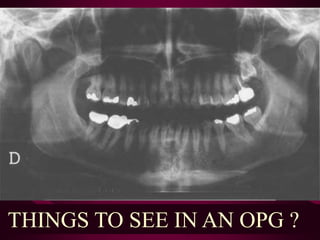

THINGS TO SEE IN AN OPG ?

THINGS TO SEEIN AN OPG ?